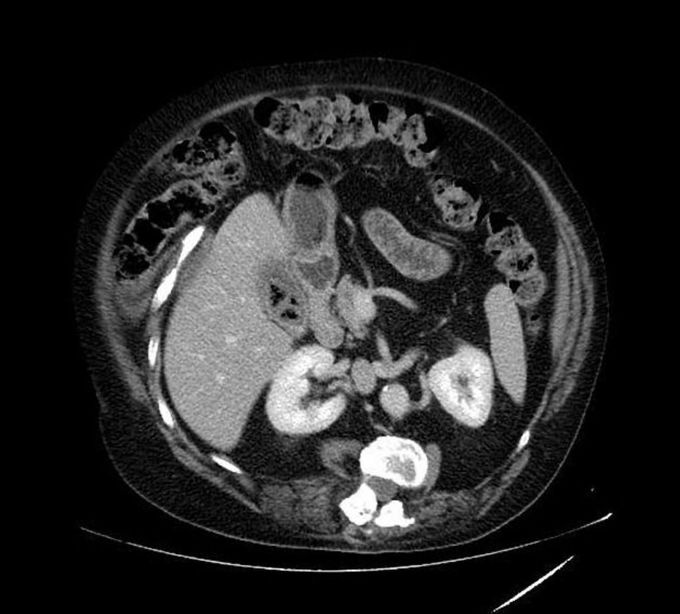

Whats your dx??

It describes gas or fluid filled in calculus in gallbladder

Emphysematous Cholecystitis